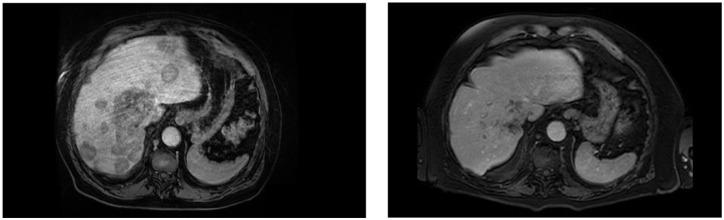

Point mutations of the fibroblast growth factor receptor (FGFR)2 receptor in intrahepatic cholangiocarcinoma (iCC) are mainly of unknown functional significance compared to FGFR2 fusions. Pemigatinib, a tyrosine kinase inhibitor, is approved for the treatment of cholangiocarcinoma with FGFR2 fusion/rearrangement. Although it is hypothesized that FGFR2 mutations may cause uncontrolled activation of the signaling pathway, the data for targeted therapies for FGFR2 mutations remain unclear. analyses demonstrated the importance of the p.C382R mutation for ligand-independent constitutive activation of FGFR2 with transforming potential. The following report describes the clinical case of a patient diagnosed with an iCC carrying a FGFR2 p.C382R point mutation which was detected in liquid, as well as in tissue-based biopsies. The patient was treated with pemigatinib, resulting in a sustained complete functional remission in fluorodeoxyglucose-positron emission tomography/computed tomography over 10 months to date. The reported case is the first description of a complete functional remission under the treatment with pemigatinib in a patient with p.C383R mutation.

与FGFR2融合相比,肝内胆管癌(iCC)中纤维母细胞生长因子受体(FGFR)2受体的点突变,其功能意义大多未知。培米替尼是一种酪氨酸激酶抑制剂,被批准用于治疗具有FGFR2融合/重排的胆管癌。尽管据推测FGFR2突变可能导致信号通路的失控激活,但针对FGFR2突变的靶向治疗数据仍不明确。分析表明,p.C382R突变对于具有转化潜能的FGFR2的非配体依赖性组成性激活具有重要意义。以下报告描述了一名被诊断患有携带FGFR2 p.C382R点突变的iCC患者的临床病例,该突变在液体活检以及组织活检中均被检测到。该患者接受了培米替尼治疗,截至目前,在超过10个月的氟脱氧葡萄糖 - 正电子发射断层扫描/计算机断层扫描检查中实现了持续完全功能缓解。该报告病例是首例关于携带p.C383R突变的患者在培米替尼治疗下实现完全功能缓解的描述。